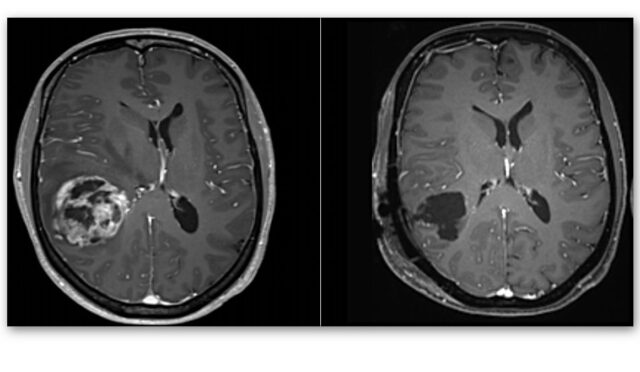

Kalbimiz, hapşırma esnasında durmasa da beyinde anevrizmaların yırtılma ihtimali var.